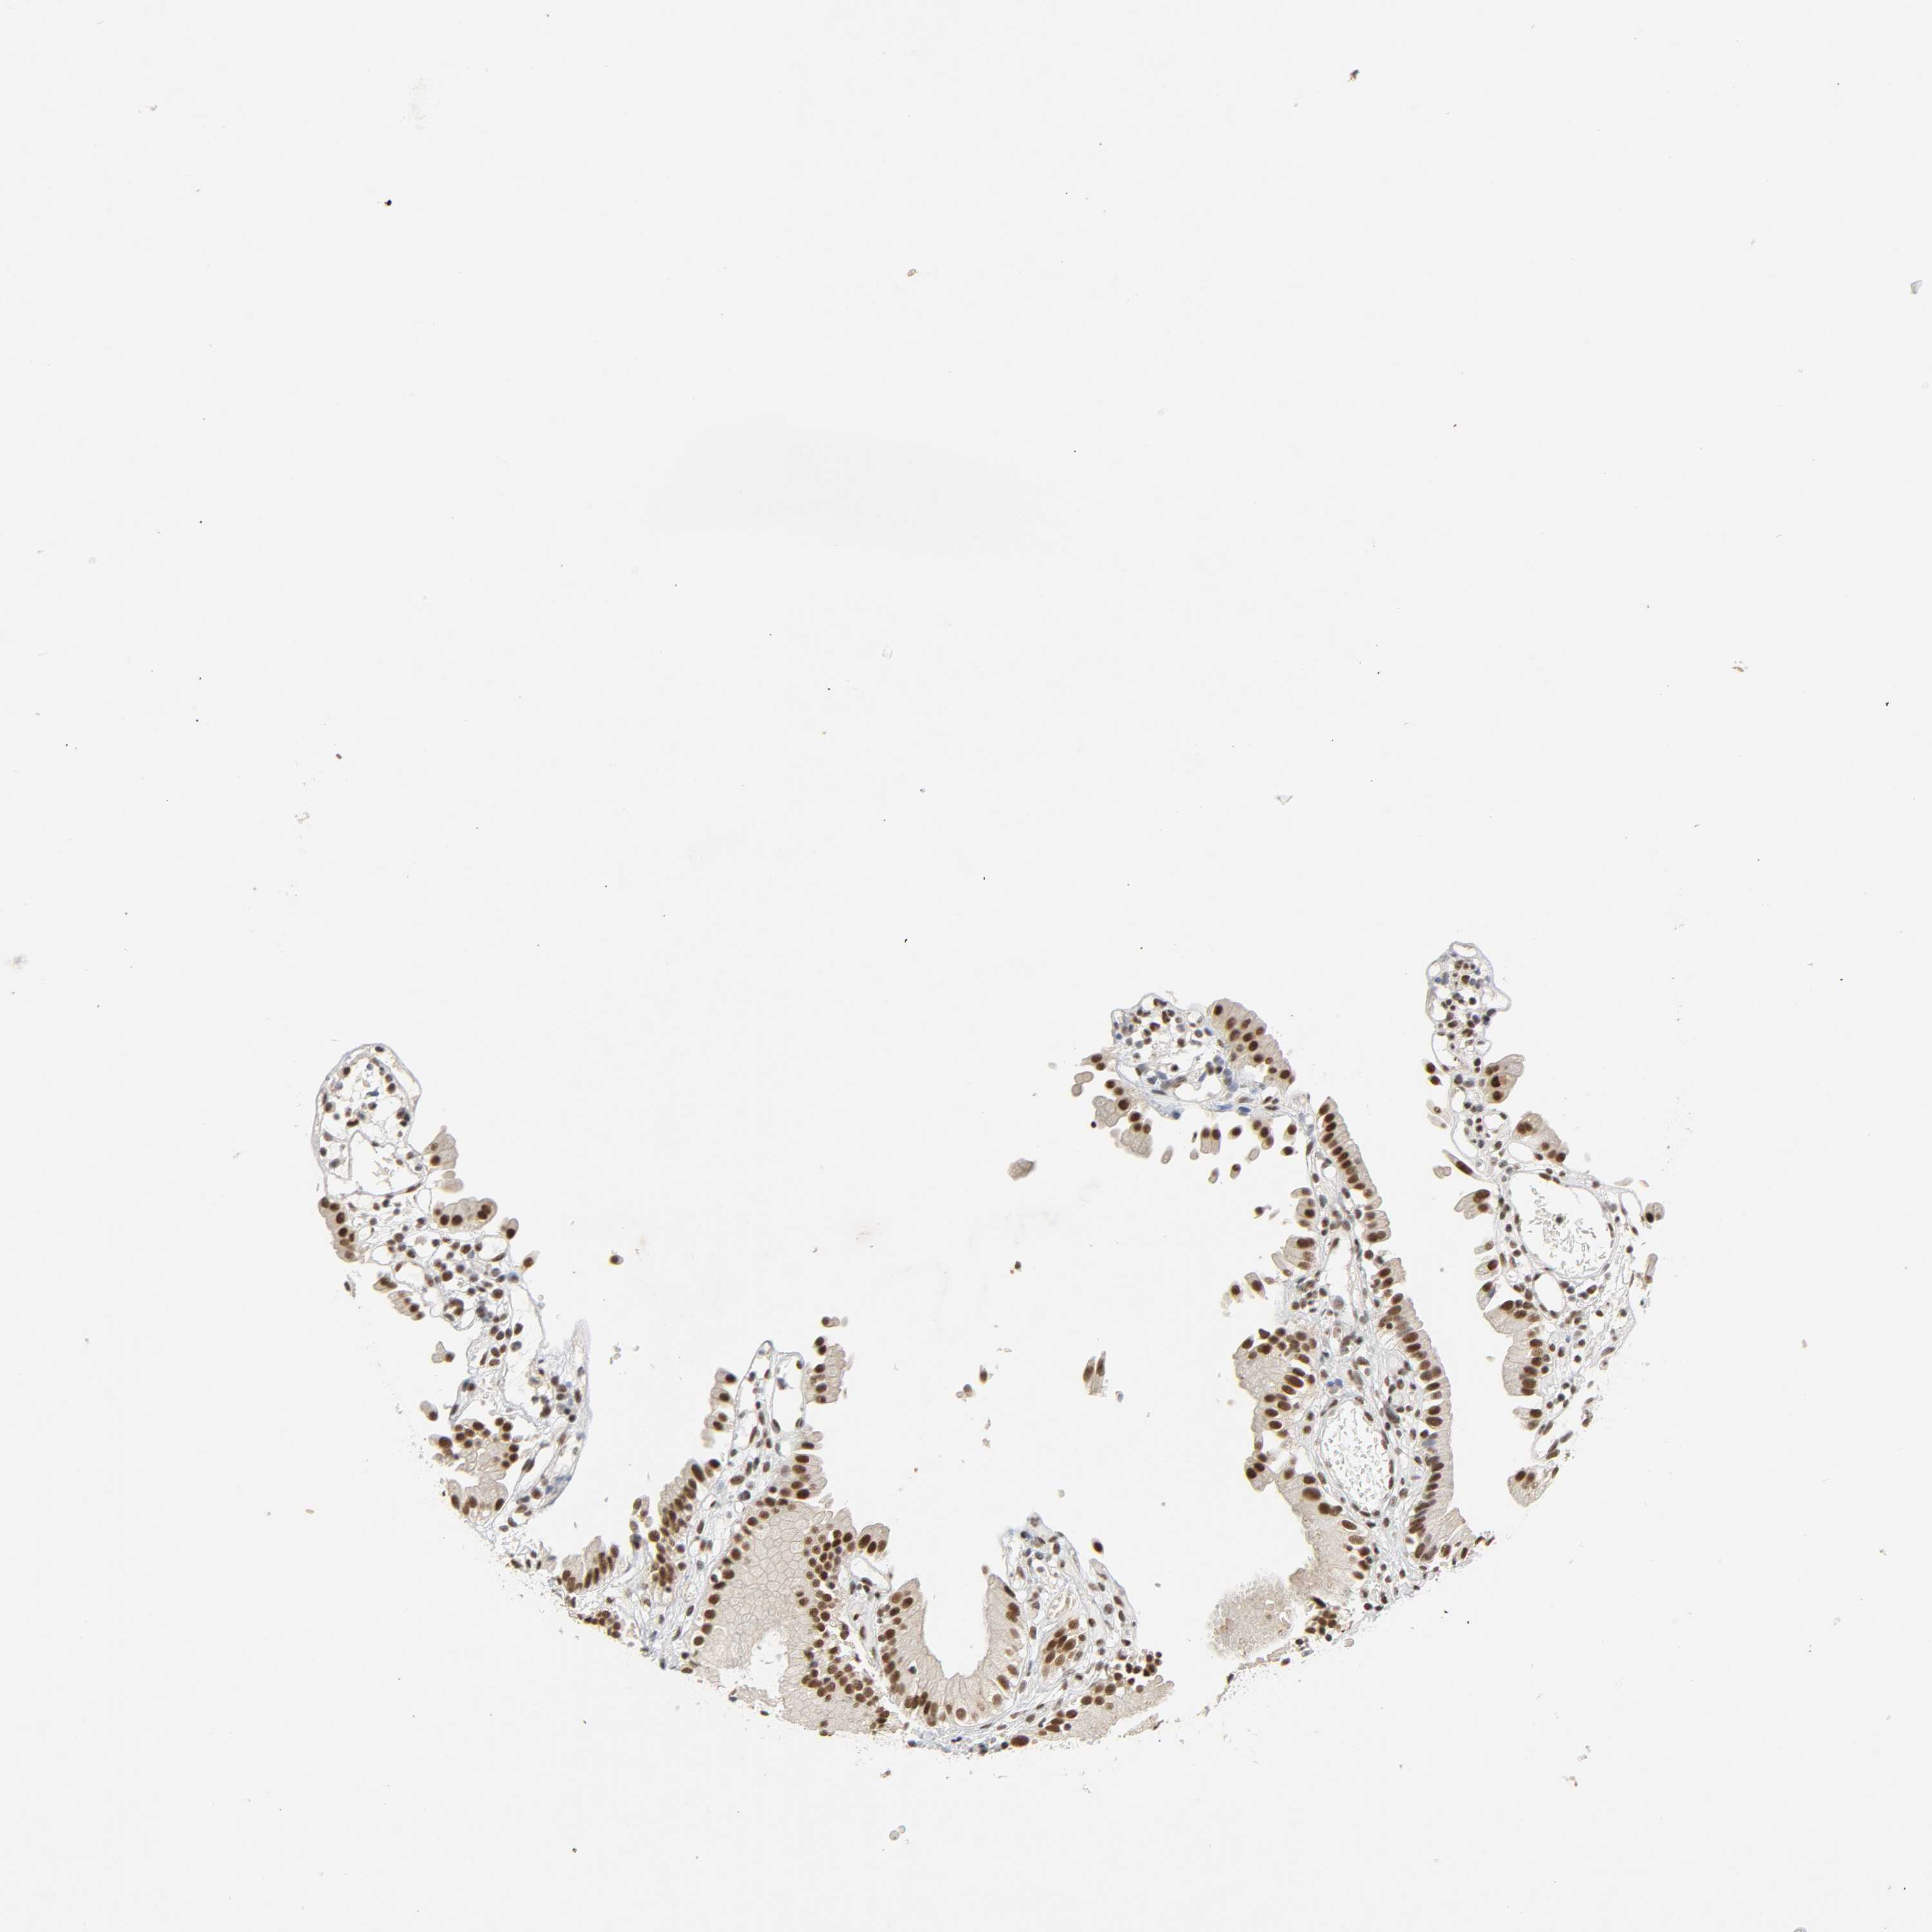

GALLBLADDER - Antibody stainingi

Antibody staining in the annotated cell types in the current human tissue is reported as not detected, low, medium, or high, based on conventional immunohistochemistry profiling in selected tissues. This score is based on the combination of the staining intensity and fraction of stained cells.

Each image is clickable and will lead to virtual microscopy that enables deeper exploration of all samples and also displays staining intensity scores, fraction scores and subcellular localization as well as patient and tissue information for each sample.

Read more

Antibody HPA004198

Glandular cells High